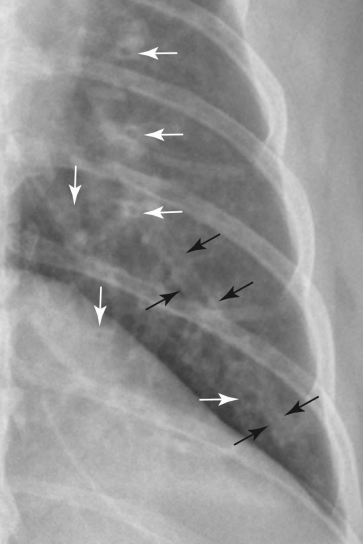

Bronchial signs

Tram line

Doughnuts

기관지벽 두꺼워질 때 보이는 sign

폐 말단으로 갈수록 깨끗한 게 정상

말단에도 tram line 보이면 비정상

VS.

(왼쪽이 정상, 말단으로 갈수록 깨끗. 말단에도 tram line 보이는 오른쪽은 비정상.)

흰색: doughnuts, 검은색: trams)